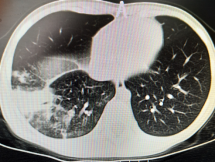

以下為呼吸專業(yè)典型病例分享:

圖片5:氣管內(nèi)膜結(jié)核及重癥支原體肺炎所致氣道阻塞、塑性支氣管束